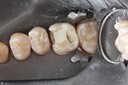

Gary Umeda #18, 19, 20 try in

Gary Umeda #18, 19, 20 finish